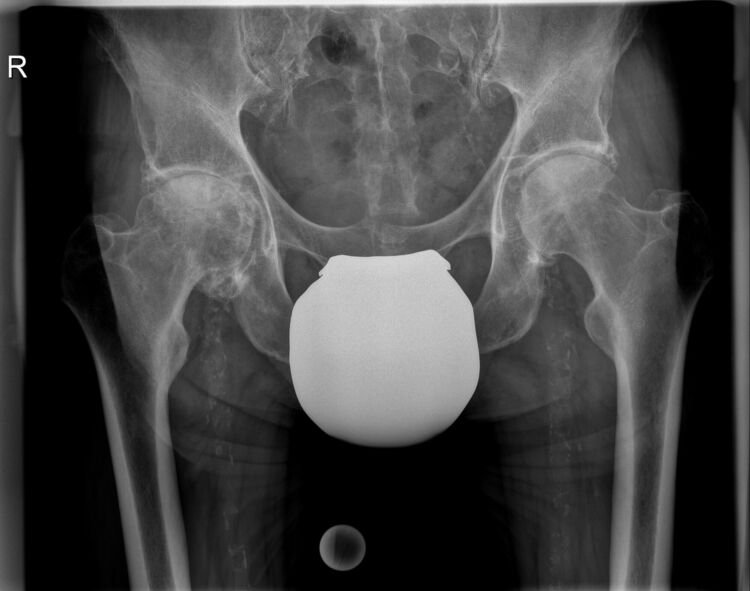

Αρθροπλαστική ισχίου με τσιμέντο στην κοτύλη

Ανδρας 67 ετων συνταξιούχος με προστατεκτομή και ακτινοθεραπεία πριν 4 χρόνιαπροσήλθεμε εντονο πόνο και δυσκαμψία του δεξιού ισχίου! Ο ακτινολογικος έλεγχος εδειξεοστεοαρθρίτιδα. Εξαιτίας του πόνου αποφασίστηκε να γίνει αρθροπλαστική ισχίου. Λογω